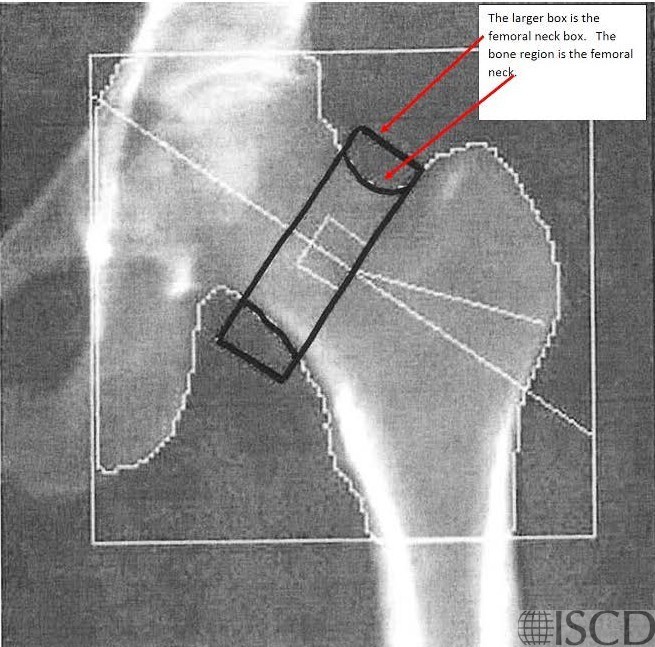

There is a black hole artifact over L4, therefore it was omitted from analysis. There are black hole-type artifacts over L4 and in the soft tissue.

This Hologic lumbar spine DXA scan shows a black hole-type artifact over L4. Items like lead bullets and tantalum clips show up as “black”on Hologic scans. The accompanying radiograph shows the clips over L4. L4 is omitted because of overlying artifacts.

Black hole artifacts occur with dense metals such as lead and tantalum on a Hologic scan. Other metals, like stainless steel, don’t produce black hole artifacts. Presumably there is complete attenuation of both Kev peaks so the difference is zero, making the image appear black. Lead bullets are measured as having high bone mineral content (BMC) and appear black in the dual-energy mode on the Hologic scanner and blue as artifact on GE Healthcare scanners. Black hole artifacts over bone are handled differently between Hologic and General Electric. With the Hologic scanner, when a dense artifact overlies bone, the BMC associated with that artifact is excluded, but the bone area is not altered. Consequently, the bone mineral density (BMD) of the affected vertebra, and of L1-4 is decreased. The GE scanners exclude both the associated BMC and area covered by the artifact, thereby minimizing the impact on BMD. Dense artifacts in the soft tissue do not significantly affect BMD on either manufacturer’s densitometer on phantom experiments., however, further experiments need to be done to verify this finding.